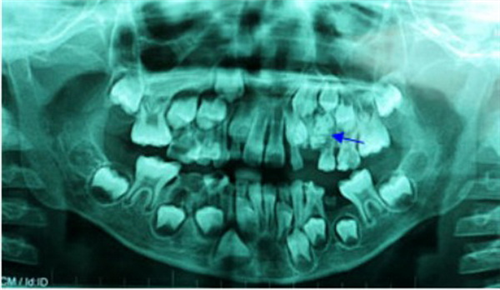

ក្មេងប្រុសរូបនេះត្រូវបានគេសង្កេតឃើញថាមាត់របស់វាមានដុះធ្មេញខុសពីធម្មតាក្រោយ ឪពុកម្ដាយរបស់ក្មេងនេះបានយកគេទៅឆ្លុះកម្មរស្មី X មើលឃើញថា មានធ្មេញដុះជាប់គ្នាយ៉ាងច្រើនសរុបទៅប្រហែលជាជាង ៧៦ គ្រាប់។ ក្រុមគ្រួសាររបស់គេបានយកក្មេងប្រុសរូបនេះទៅកាន់ពេទ្យធ្មេញ Ham ដែលជាមន្ទីរពេទ្យរដ្ឋ ហើយក្រុមគ្រូពេទ្យបានពនិត្យមើលហ្វីលដែលថតបានឃើញថាមានធ្មេញធំចំនួនជាង ២០ និងធ្មេញតូចៗចំនួនជាង ៥០ ហើយក្រុមគ្រូពេទ្យក៏បានធ្វើការវះដកធ្មេញចេញមកខ្លះដែរ៕